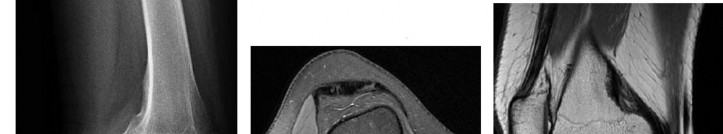

A 15-year-old male presents with deep knee pain awakening him at night. Radiographs show a permeative destructive lesion in the distal femoral metaphysis with a 'sunburst' periosteal reaction and Codman's triangle.

Biopsy confirms high-grade conventional osteosarcoma. What is the most critical prognostic factor for long-term overall survival in this patient?

Explanation

For localized high-grade osteosarcoma, the most important prognostic indicator is the histologic response to neoadjuvant chemotherapy. This is evaluated during the definitive resection. A 'good response' is typically defined as greater than 90% or 99% tumor necrosis. Patients who achieve this level of necrosis have a significantly improved disease-free and overall survival rate compared to 'poor responders' who have extensive viable tumor cells remaining.